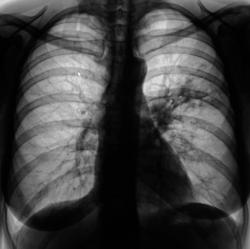

После расшифровке флюорограмм пациент "взят на контроль" - 1, 2.

Произведено стандартное дообследование пациента - рентгенография (3, 4, 5) и томография (6, 7, 8, 9, 10, 11). Была заподозрена онкология, однако изменения на томограмме - срез 7 см. (9, 10, 11), склонили нас в пользу изменений воспалительного генеза. Было решено провести адекватную противовоспалительную терапию. После проведения противовоспалительной терапии был произведен рентген-контроль ( 12, 13, 14, 15).

А почему уважаемый Валентин Львович была заподозрена онкология? На представленных снимочках хорошо видно перибронхиальную и перивоскулярную инфильтрацию легочной ткани, сегментарная пневмония.